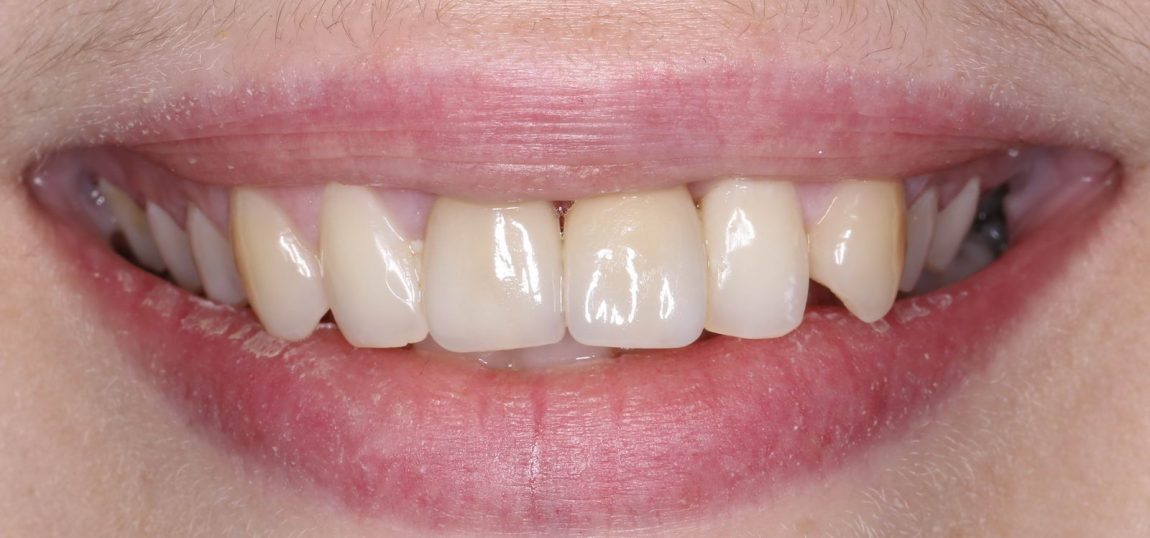

Установка формирователя десны, стандартного или индивидуального — это «классическое» завершение операции немедленной имплантации, поскольку, при условии хорошей стабильности имплантата и отсутствии проблем со слизистой оболочкой, разумно проводить формирование десневого контура одновременно с интеграцией имплантата. Фактически, это даёт возможность объединить все хирургические этапы в одну операцию, через несколько месяцев установить на имплантат коронку (для этого даже не требуется анестезия) и завершить лечение с минимальной травмой и максимальным результатом.

Но это еще не всё. Не каждый пациент готов оставаться без зуба на период проведения имплантологического лечения. Поэтому в некоторых случаях мы можем зафиксировать на только что установленный имплантат временную коронку, замок или даже целый временный протез:

Таким образом, мы добиваемся улучшения качества жизни наших пациентов в кратчайшие сроки. Не говоря уже о том, что сокращение этапов стоматологического лечения приводит к уменьшению его стоимости.